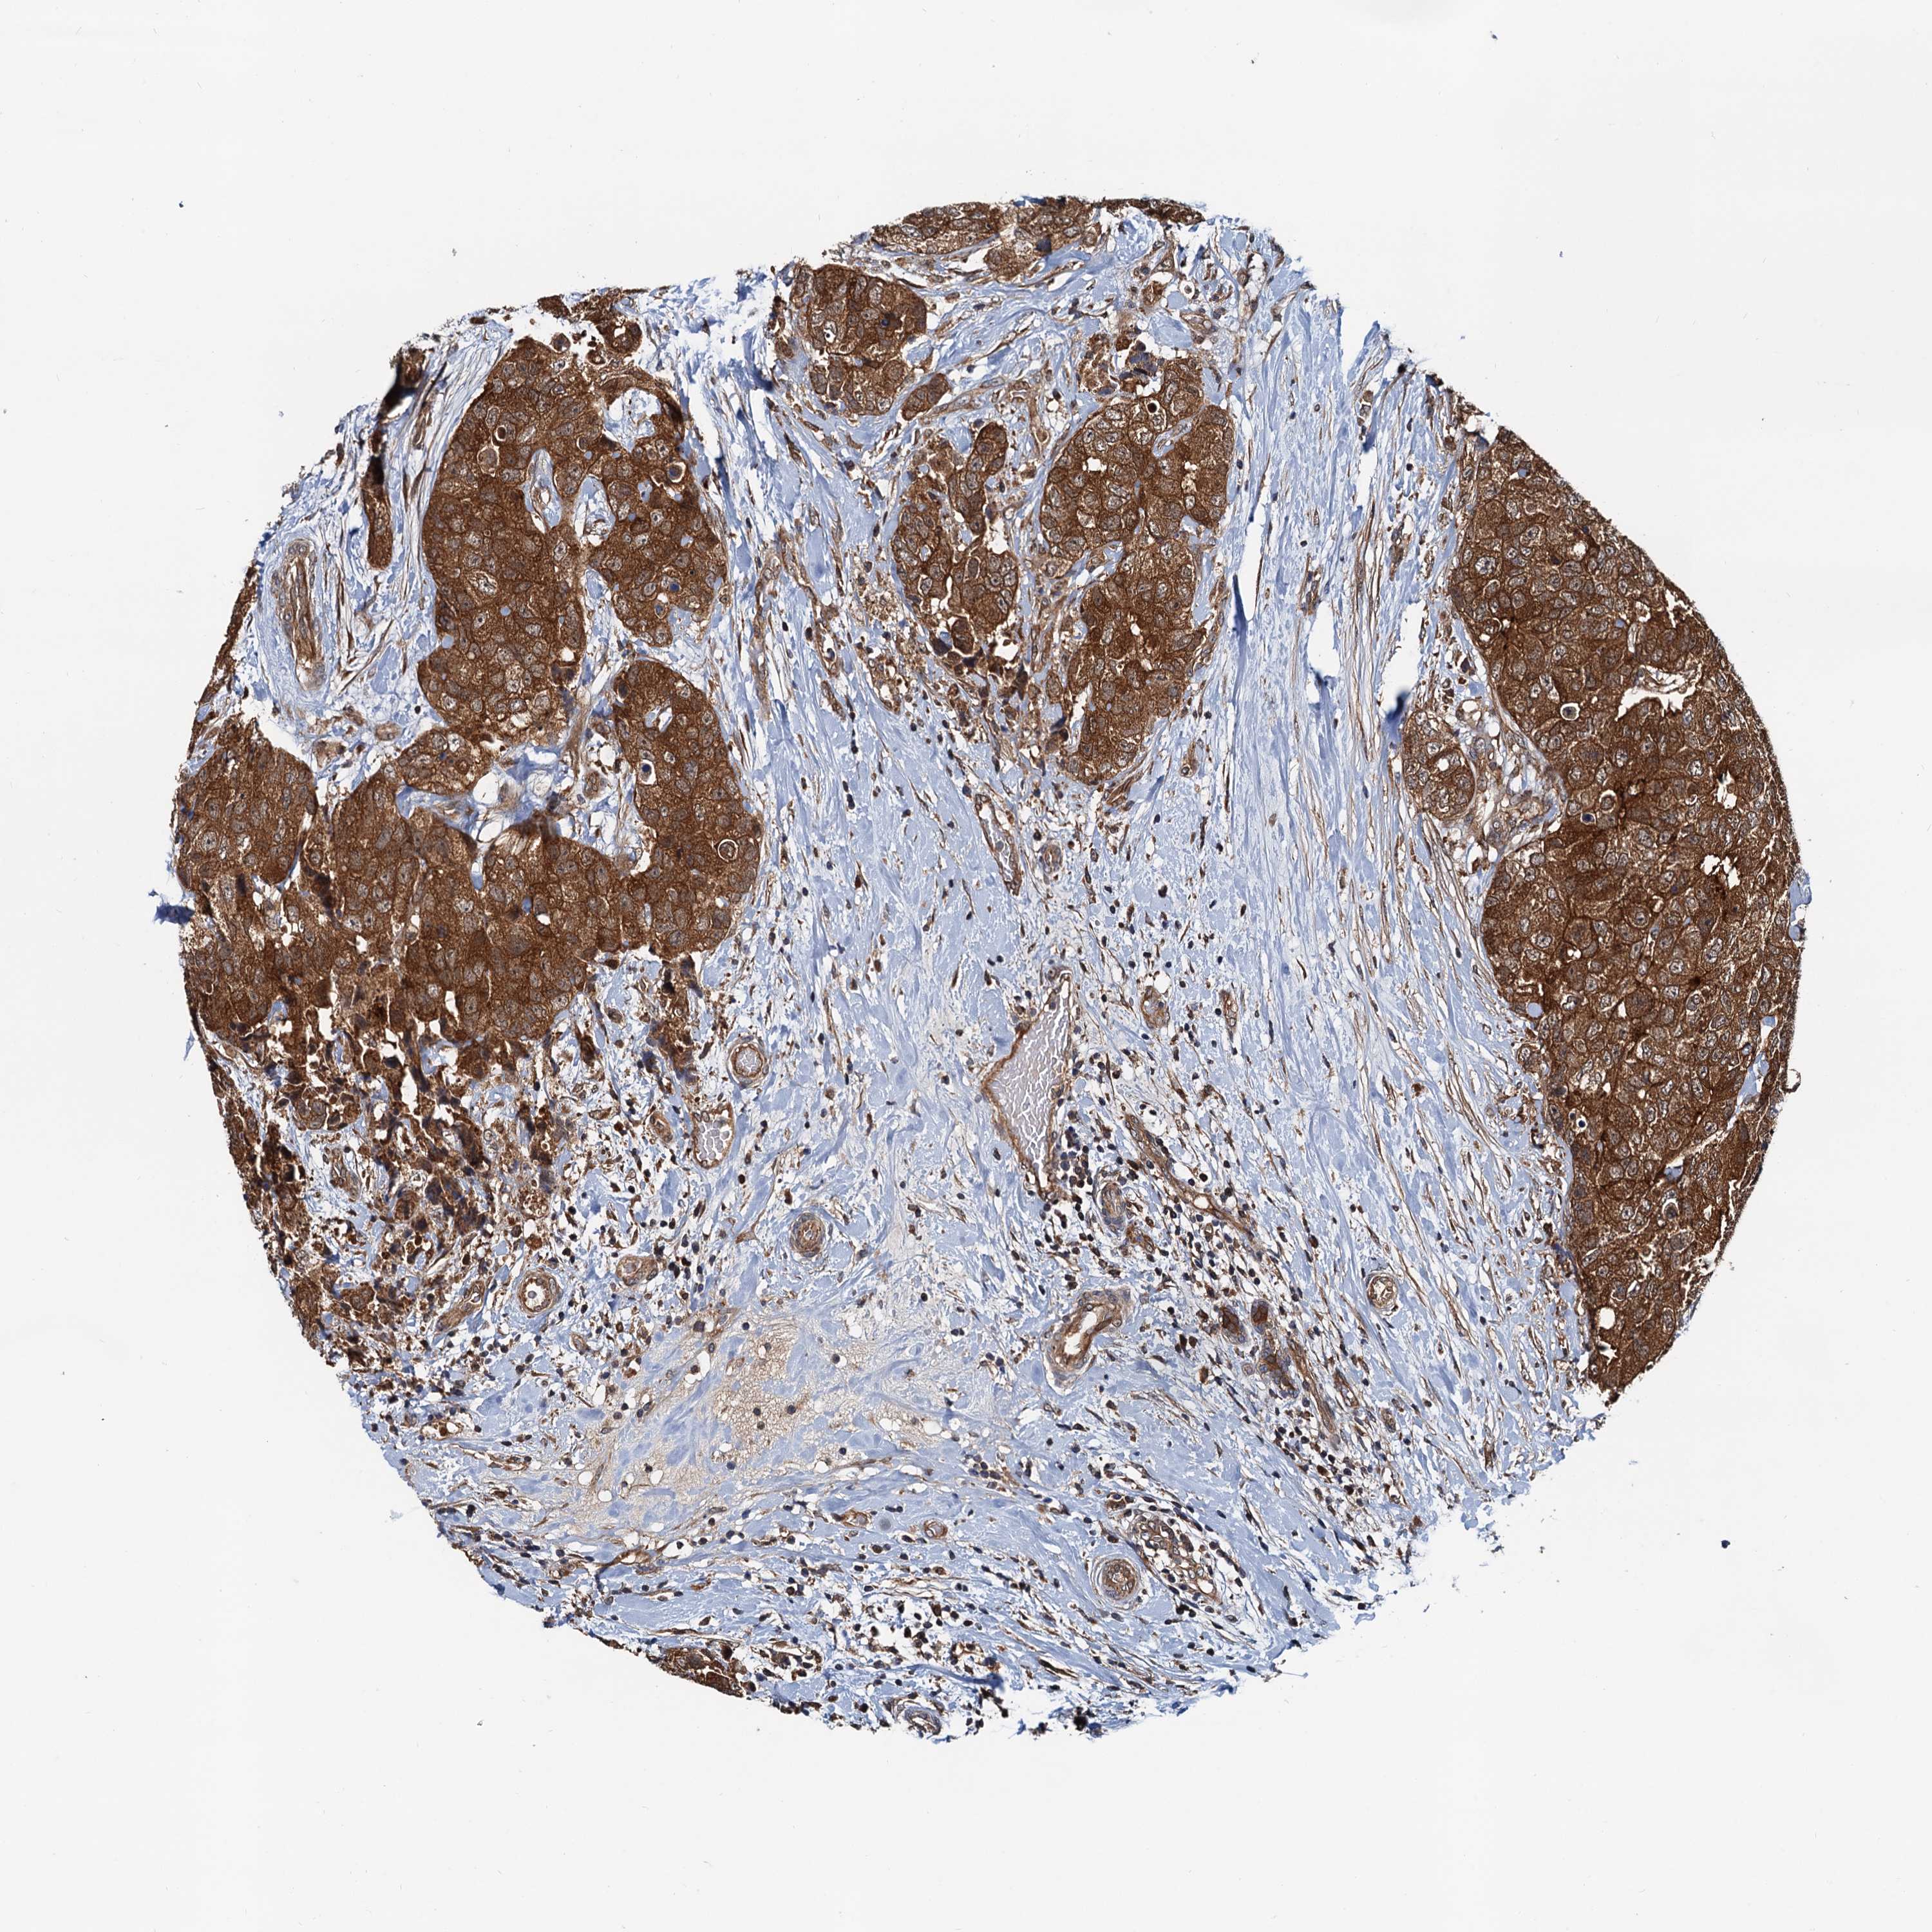

CANCER BREAST CANCER Show tissue menu

BRCA TCGA BRCA VALIDATION PROTEIN EXPRESSION